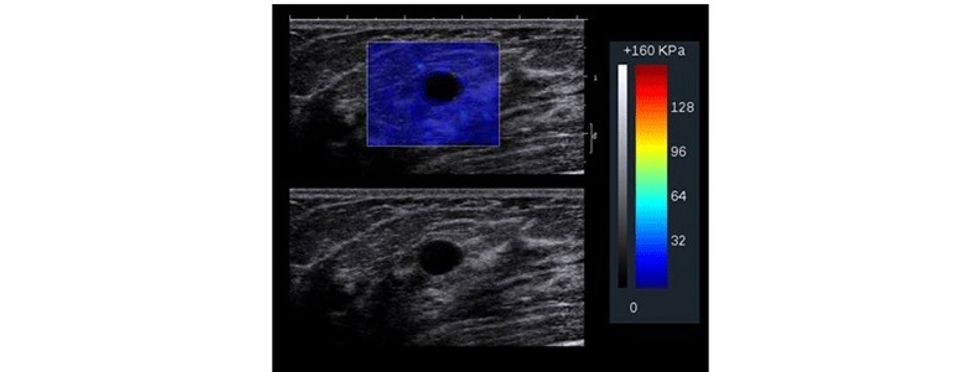

Të dhënat e fituara përpunohen përmes paketës softuerike në formë të color mapping apo grayscale për të vizualizuar zonën me interes e cila ekzaminohet.

Parimet bazë te elastografisë bazohen në dukurinë që indet nën kompresion shfaqin tendosje dhe kjo do të paraqitet me karakteristika të ndryshme. Prandaj, nën kompresion, në boshtin aksial, duke bërë matjet, mund të vlerësohet ngurtësia dhe elasticiteti i indit, para dhe pas kompresionit, ndërsa imazhi i paraqitur dhe i llogaritur quhet elastogram, ku fushat me ngurtësi të rritur dhe elasticitet të ulur paraqiten me ngjyrë të kaltër.

Me aplikimin e elastografisë krahas ultrazërit konvencional, mundësohet që të rritet specificiteti i ultrazërit, sidomos në lezionet e kategorizuara me BiRads 4, duke bërë përcaktimin e elasticitetit të indit, detektim të qartë të nivelit të elasticitetit të indit dhe, marrë parasysh që formacionet me natyrë malinje kanë dendësi më të lartë dhe elasticitet të ulur gjatë aplikimit të kompresionit në boshtin aksial e shprehur në kPa. Pastaj me anë të mapingut qartë detektohet natyra e lezionit.